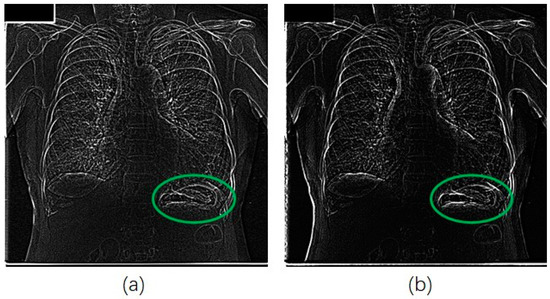

We also applied our method for the JSRT database in a similar manner for that of the portble CXRs database. Figure 7 shows an original image from JSRT database. We can see from Figure 8a that much more noise was created in the unsharp mask by using the Gaussian kernel. The EMEE value for the original CXR was 1.453. Although the EMEE value was improved to 5.643 for the final enhancement image, the noise in Figure 8a was also added in the final enhancement.

When, we applied our RAD-based USM method to this image from the JSRT database, the diffusion parameter α was set to 0.02. Most of the important edge information was reinforced in the unsharp mask with less noise (as shown in Figure 8b).

Figure 8. Unsharp masks for image of Figure 7. Green circles are the stomach area, (a) mask from Gaussian difussion; (b) mask from RAD.